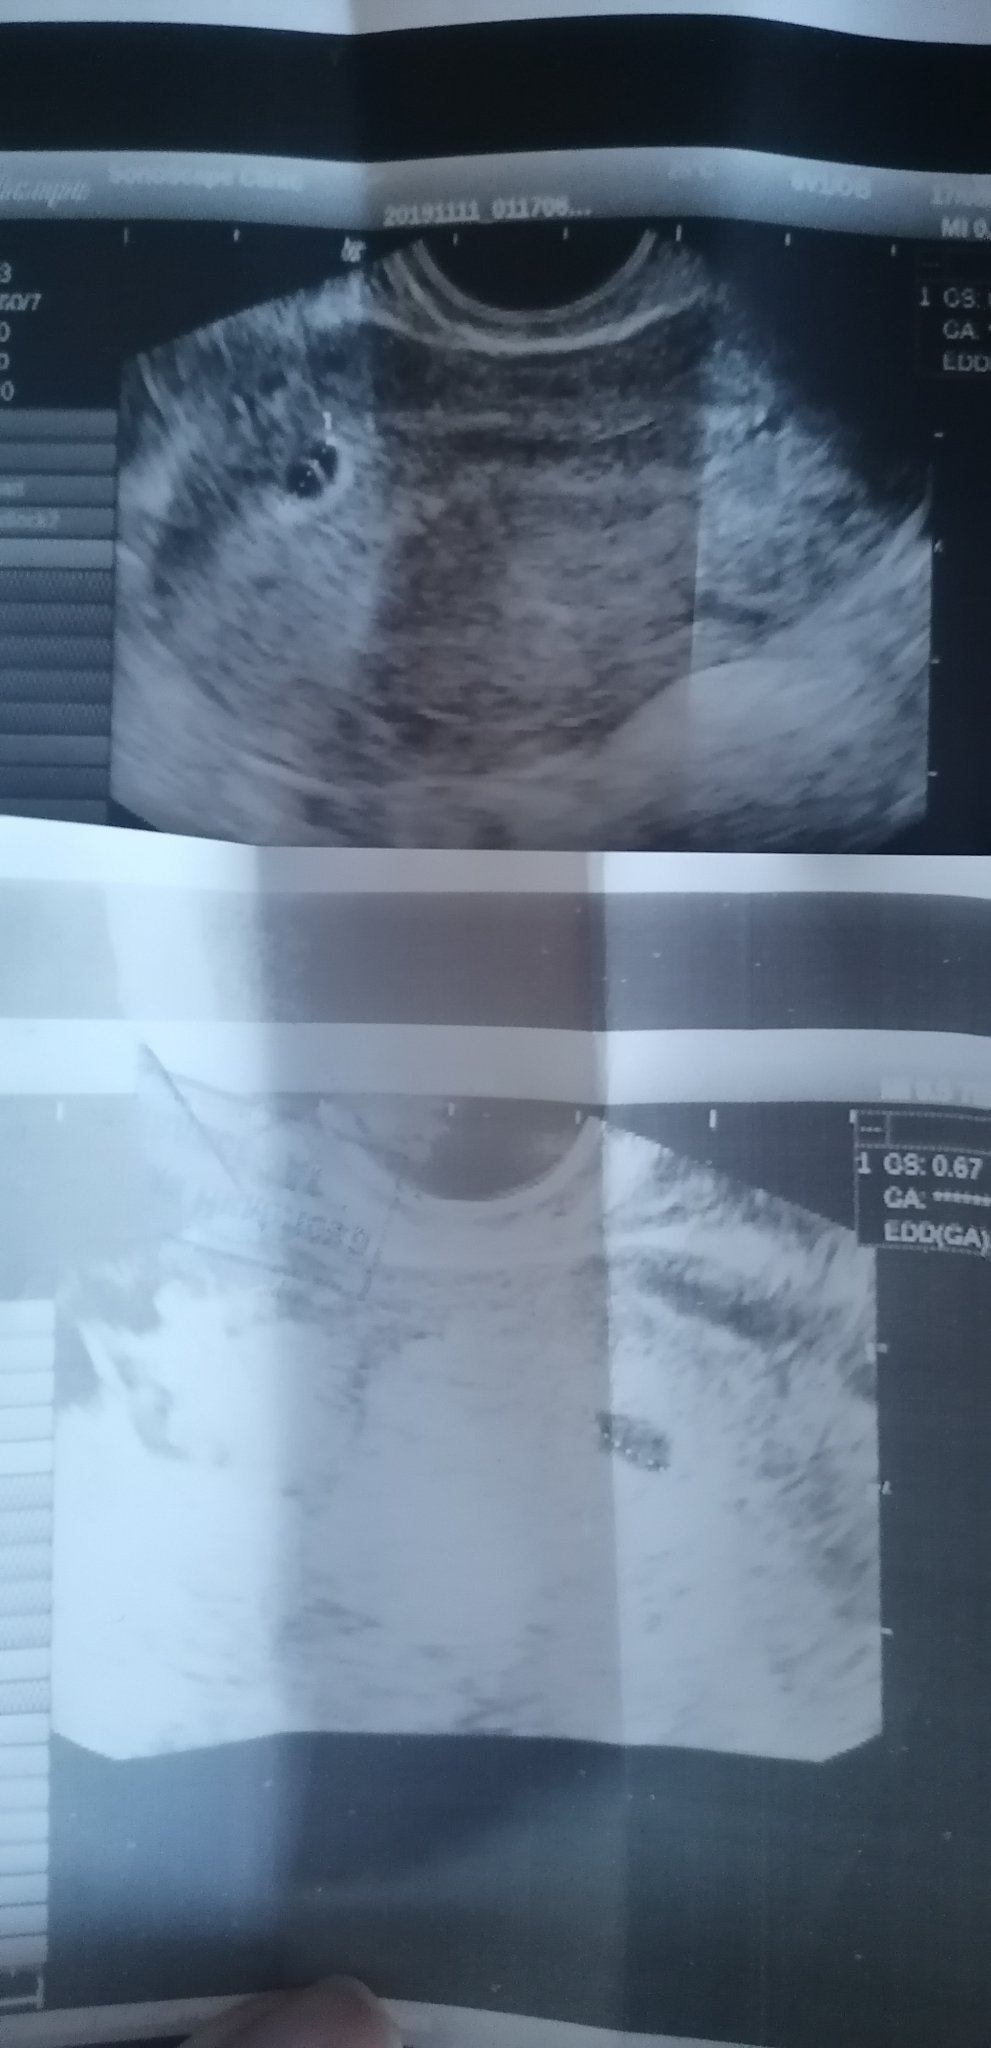

Моля помагайте, на приложената снимка се вижда сакът единия път от ляво другия път от дясно. Снимките са с разлика от две седмици. Това нормално ли е?Не трябва ли да си стои от едната страна?